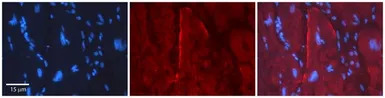

IHC-P analysis of human heart tissue using GTX47484 GJC2 antibody at 1:100. Left to right:DAPI, GJC2, Merge. The low pH, heat-induced antigen retrieval method utilizing Sodium Citrate buffer was performed.